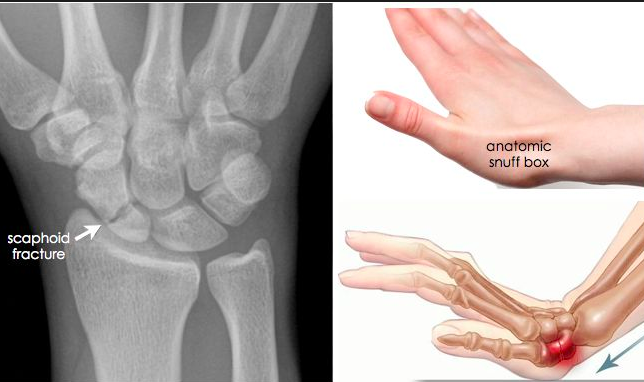

scaphoid fracture

lesion to million dollar nerve